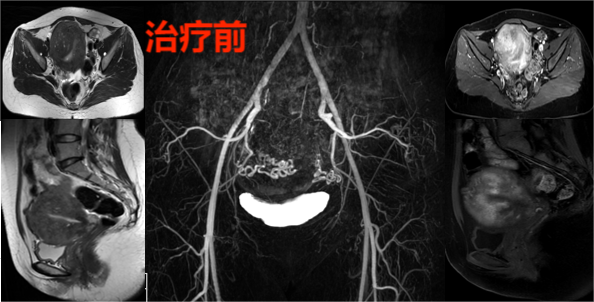

已是两个孩子母亲的胡女士,未做好避孕措施,让33岁的她却有了5次人工流产病史。反复流产后,也让痛经的恶魔缠上了她。特别是近3年,她的痛经越来越严重,每个月都要请几天痛经假。虽然她到医院检查诊断是子宫腺肌病引起的痛经,药物治疗效果不好,单位领导和同事也理解她的痛苦,但她的岗位是人少事多型,每次都很难请假调休,她不得不辞职在家,做全职母亲。这两年作为一名全职母亲,她的生活围绕照顾孩子、处理家庭事务而展开。尽管生活充满繁忙,胡女士仍保持乐观心态,努力为家人带来温馨与欢乐。然而,胡女士的痛经还是越来越重还伴有呕吐,服用止疼药后还要躺着,不然会把止疼药吐出,生理期连给孩子们做早餐都办不到了。胡女士丈夫对她的痛苦非常关心,也在当地看遍了很多保守的治疗方法,甚至民间偏方也试了不少,都没能很好的解决胡女士的痛经。胡女士生理期痛经服用止疼药后只能床上躺着,她就刷抖音转移注意力,打发时间,也常常看痛经的科普视频,后来她刷到了广东省第二人民医院介入血管科韦文姜副主任医师抖音子宫腺肌病痛经的科普视频,她关注了解后就跟丈夫说要来广州看看。胡女士夫妻俩抱着试试的心态在广东省第二人民医院官网进行了挂号预约介入血管科韦文姜副主任医师的门诊,来广州就诊后,门诊磁共振MRA检查显示:“子宫弥漫性腺肌病,子宫明显增大,大小约95mm*77mm*89mm”(如下图)。